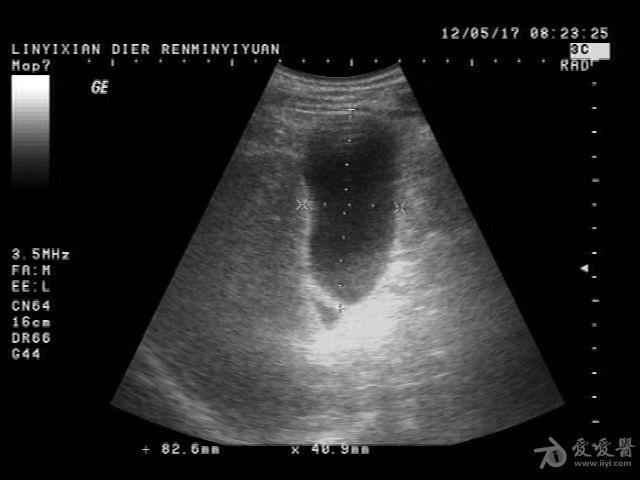

患者男性,57岁,十多年前曾患“肝炎”,近一年在它院曾诊断为:肝硬化。一月前在市医院治疗发现有腹水形成并发现有“腔梗”。古来我院就诊。B超提示:肝脏病理声像(肝光点增粗、肝硬化声像)胆囊图像如图。腹盆腔未及游离暗区回声。

这个胆囊颈部的暗区可以称“胆囊憩室”吗?

邹褶吧,不是憩室

很明显的胆囊皱褶,这种现象应该很常见的,肝硬化的时候胆囊比正常要大些

应该是胆囊皱褶。